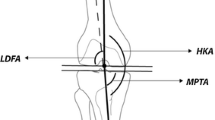

The reason for the development of a cam-type deformity in growing athletes remains unclear. One explanation could be that high stresses lead to reactive bone formation at the area of the cam-type deformity. In this case the growth plate should not be affected. However, one may speculate whether repetitive high loading forces alter physeal growth. In two studies, potential physeal changes, predominantly growth arrest, but also accelerated growth associated with chronic overload in young athletes were reported [1, 4]. Jaramillo et al. [8] described stimulation of endochondral ossification with thickening and extension of the epiphysis toward the metaphysis in experimentally induced juxtaphyseal trauma in rabbits. Theoretically, chronic overuse of the proximal femur might represent repetitive indirect trauma, which potentially could stimulate a similar growth plate extension with resultant metaphyseal deformity [8]. This is reinforced by an association between an abnormal shape of the growth plate, as measured by extension of the femoral head physis toward the neck of the femur (Fig. 1A–B), and decreased head-neck offset in adult patients with cam-type impingement [19]. A decreased head-neck offset has been inversely correlated with an increased alpha angle and is an alternative measurement for cam-type deformity [14]. Increased extension of the physeal cartilage onto the metaphysis has been associated with abnormal growth of the femoral head in Perthes disease [7]. This led to the question whether an abnormal extension of the physis onto the metaphysis also might be detected in growing athletes and whether there might be an association with a cam-type deformity.

(A) A radial-sequence MR image of the hip of a 20-year-old basketball player taken at the 2 o’clock position is shown. (B) The diameter (d) of the femoral head, through the center of the head-neck axis, and the distance from a line orthogonal to the diameter to the lateral-most extension of the epiphysis (e) is measured. The epiphyseal extension is defined as e/d. (C) The measurement of the alpha angle on this same MRI slice is shown.

Our key measurement variables were epiphyseal extension measured on radial-sequence MRI at each position of the cranial hemisphere from 9 o’clock (posterior femoral head-neck junction) to 3 o’clock (anterior head-neck junction) and the corresponding alpha angles (Fig. 1) [14, 19]. A proton-weighted radial sequence on a 3.0 Tesla MR system (Siemens, Erlangen, Germany) was used for evaluation of morphologic features of the proximal femur [18]. The radial planes were rotated clockwise in 30°-intervals around and perpendicular to the femoral neck axis resulting in seven hour-defined measurement points (Fig. 2). Epiphyseal extension is calculated as follows: (1) the head-neck axis is drawn through the center of the femoral head to the medial femoral head, (2) a line orthogonal to this axis is drawn starting at the medial femoral head toward the clock position being measured, (3) the distance between this line and the physeal extension is measured, parallel with the head-neck axis, and (4) this distance (e) is divided by the femoral head diameter (d) to express epiphyseal extension as a ratio (Fig. 1B). The alpha angle was measured according to the technique described by Nötzli et al. [14]. Briefly, this is the angle between the femoral neck axis and a line connecting the femoral head center with a point, where the femoral head contours leaves a best-fit circle around it (Fig. 1C, Fig. 2).